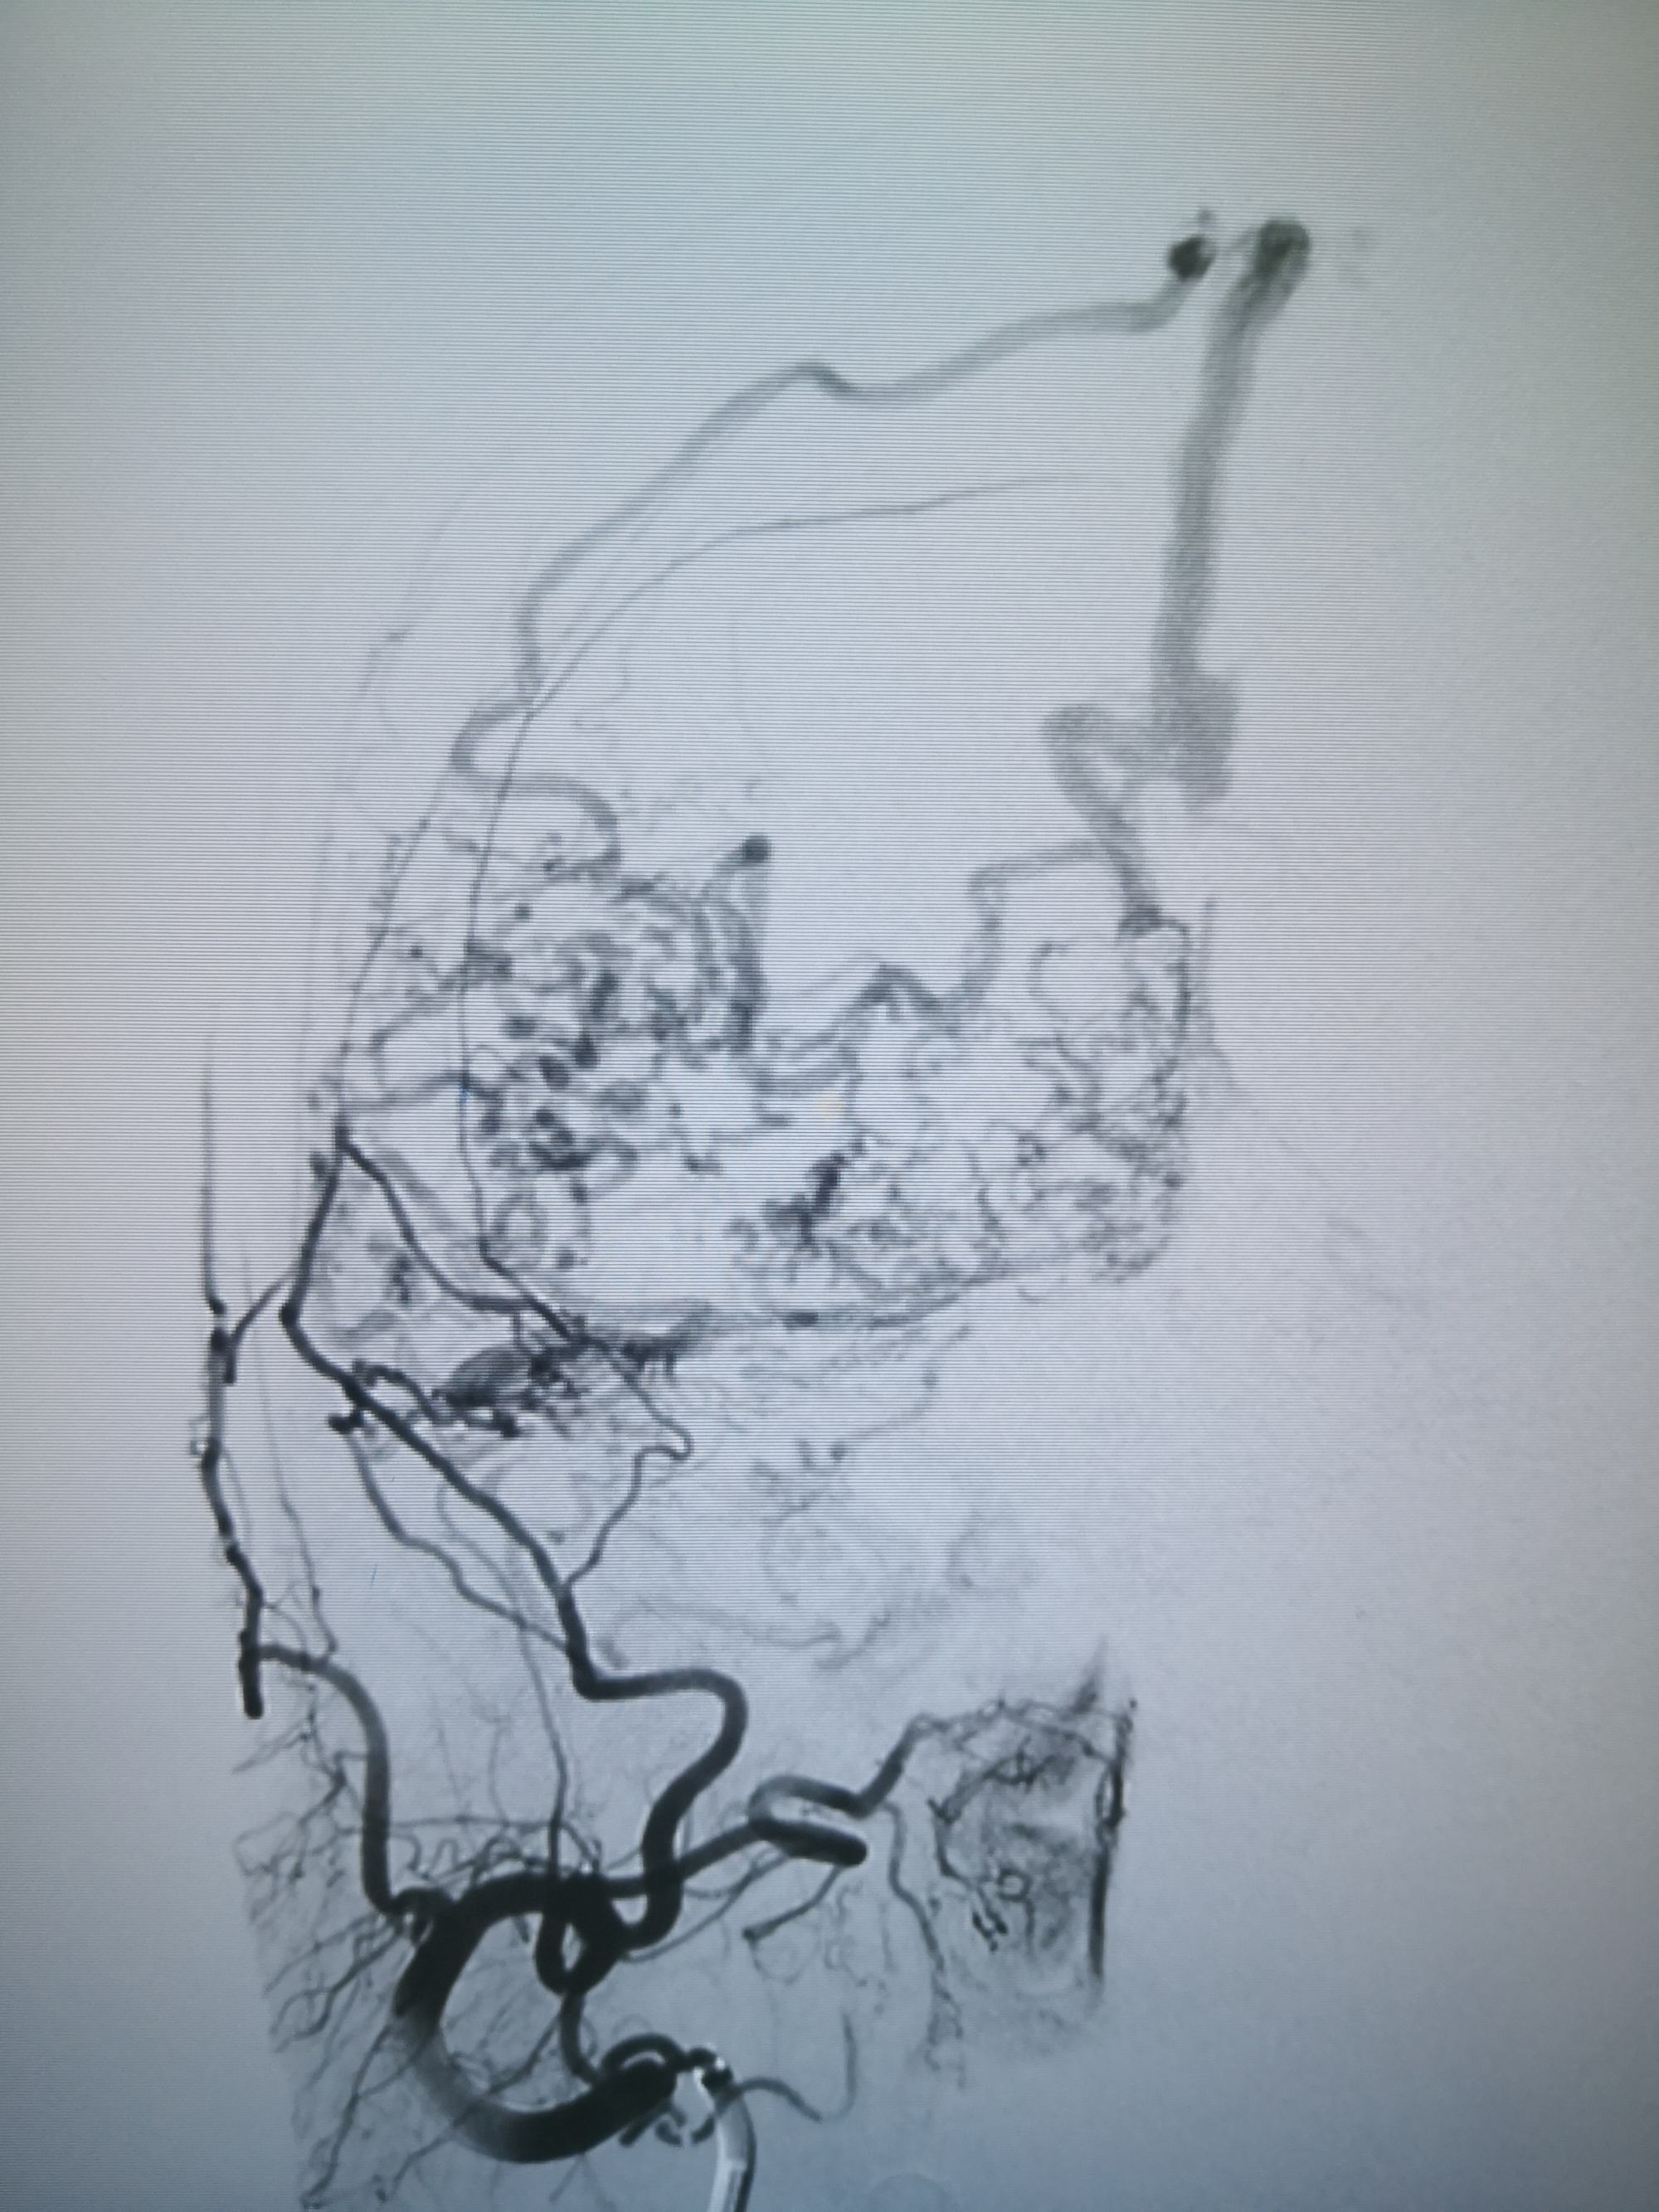

微导管到达瘘口,打胶

术后,清爽了,瘘口都不在显影,

微导管到达瘘口,打胶

术后,清爽了,瘘口都不在显影,